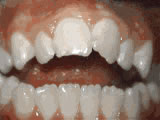

Missing lateral incisors

missing incisors before

Before

This patient's lateral incisors were congenitally missing. She had braces for 20 months to move the teeth into their correct positions, then the missing teeth were replaced with bonded "Maryland" bridges.